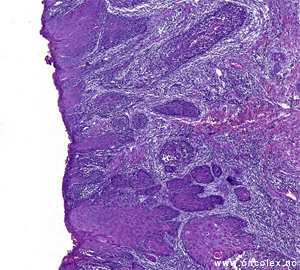

| Resektat av ytre kvinnelige kjønnsorgan med sårdannende tumor |

Lysmikroskopi av tumoren fra bildet til venstre. Dette er et infilterende plateepitelkarsinom. |